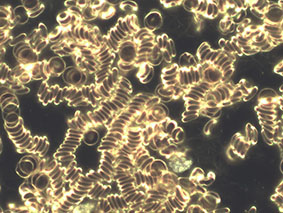

Bei der Dunkelfeldmikroskopie wird aus der Fingerbeere ein Tropfen Blut entnommen und unter 1000-facher Vergrößerung betrachtet. Das Objekt wird von seitlich unten bestrahlt, so dass der Hintergrund dunkel erscheint und auch kleinste Strukturen im Plasma noch gut erkannt werden können.